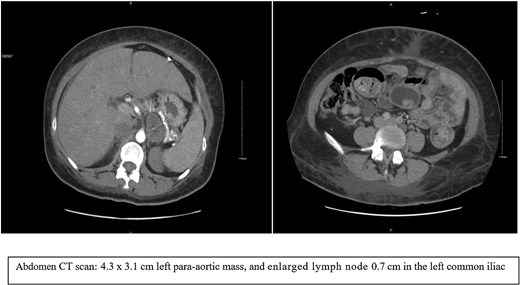

We are reporting a 38-year-old female patient known to have uncontrolled type 2 diabetes mellitus and hypertension, which was complicated by end-stage renal disease (ESRD), and she started on hemodialysis in 2021. The patient planned for a kidney transplant, and a pre-renal transplant workup was initiated. Abdomen (CT) was done as part of the workup, and an incidental finding of an adrenal mass were found. The patient was referred to our clinic for further management. She was asymptomatic. CT abdomen reviewed as shown in Fig. 1, which showed a 4.3 × 3.1 cm left para-aortic mass with punctate calcification and heterogeneous enhancement; the mass abuts the left adrenal, stomach, and posterior border of the pancreas; the region of the mass is indeterminate. There are a few prominent para-aortic and retroperitoneal lymph nodes; the largest measures 0.7 cm in the left common iliac group. A left suprarenal heterogeneous mass could arise from the left adrenal gland; further evaluation by MRI is advised. The case was flagged as suspected oncology case.